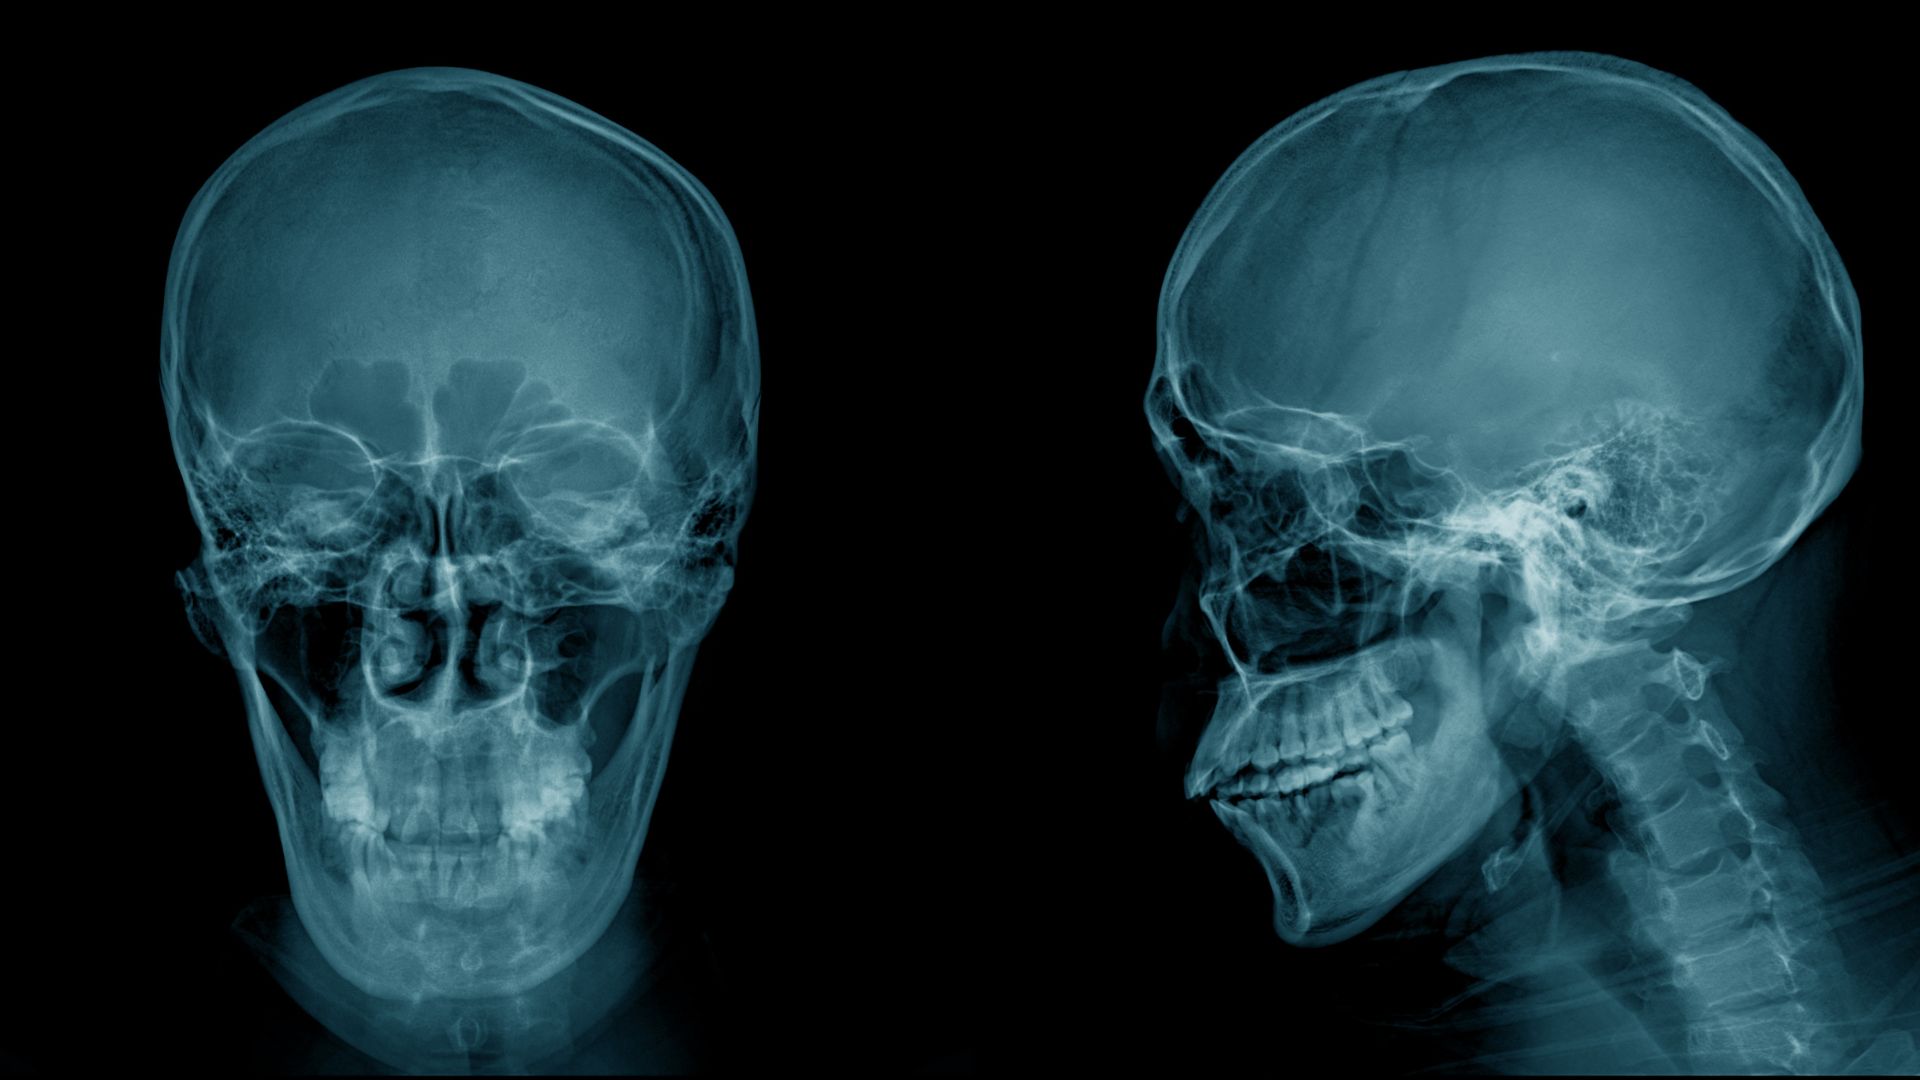

- Với những trường hợp đau đầu kéo dài không rõ nguyên nhân, có thể cần chụp X-quang, CT hoặc cộng hưởng từ (MRI) để đánh giá sâu hơn.